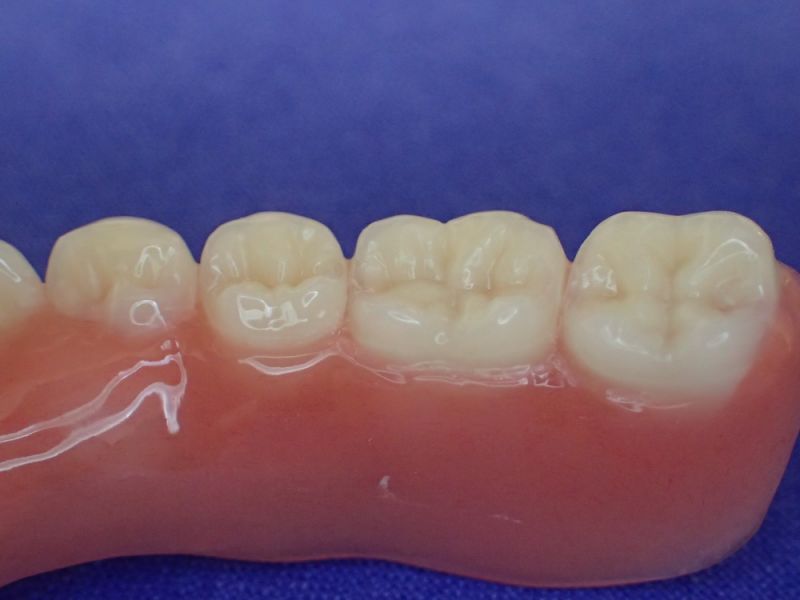

Nach inzwischen 12 jähriger Tragedauer wurden alle Kunststoffteile erneuert, das metallische Grundgeroüst der Arbeit erhalten und die Arbeit befindet sich in einem Zustand, der sich weitgehend an der Ersterstellung orientiert.

Bei derartigen Arbeiten ist es tatsächlich möglich grundlegende Konstruktionsmerkmale einer alten Arbeit zu übernehmen und Verschleißteile aus Kunststoff zu erneuern.

Im Prinzip ist das beliebig oft möglich und für den Patienten mit einer enormen Kostenersparnis verbunden.